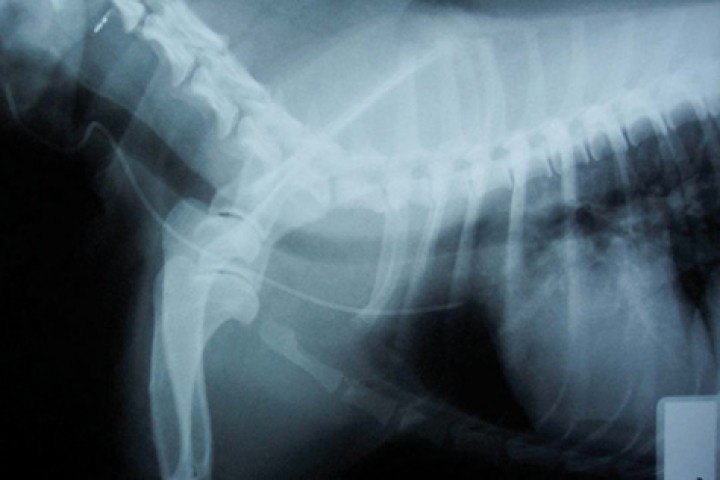

Debido al alto riesgo de contaminación del catéter con vómitos/heces, es preferible la colocación de un catéter central yugular (Fig. 6), ya que, además de proporcionar una vía de administración de fluidos y medicación, permite la extracción de sangre para monitorización de glucosa, electrolitos o albúmina, entre otros, sin necesidad de puncionar de nuevo al paciente.[ Mazzaferro EM. Update on canine parvoviral enteritis.Vet Clin North Am Small Anim Pract 2020; 50(6): 1307-1325. [pubMed] ] Puede utilizarse la vía subcutánea en los casos de deshidratación moderada,[ Davis H, Jensen T, Johnson A, et al. 2013 AAHA/AAFP fluid therapy guidelines for dogs and cats. J Am Anim Hosp Assoc 2013; 49(3): 149-159. [pubMed] ] pero está contraindicada cuando exista un compromiso circulatorio, ya que, al existir vasoconstricción periférica, la absorción y distribución de los fluidos no va a ser la adecuada.[ Fragío Arnold C. Fluidoterapia en patologías digestivas. En Fragío Arnold, C: Manual de Fluidoterapia En Pequeños Animales. Multimédica ediciones veterinarias.; 2018, capítulo 8: pp317-322. ] Generalmente el fluido de elección es un cristaloide isotónico balanceado (Ringer Lactato o equivalente). El volumen inicial y la velocidad de administración dependerán del grado de deshidratación e hipovolemia.[ Mazzaferro EM. Update on canine parvoviral enteritis.Vet Clin North Am Small Anim Pract 2020; 50(6): 1307-1325. [pubMed] , Fragío Arnold C. Fluidoterapia en patologías digestivas. En Fragío Arnold, C: Manual de Fluidoterapia En Pequeños Animales. Multimédica ediciones veterinarias.; 2018, capítulo 8: pp317-322. ] Si hay signos de hipovolemia (taquicardia/bradicardia, hipotermia, aumento del tiempo de relleno capilar, hipotensión, etc.), se administrarán bolos de cristaloide isotónico de 15-20 ml/kg en 10-15 minutos (máximo 80-90 ml/kg), monitorizando los parámetros de perfusión hasta que se vayan normalizando (terapia guiada por objetivos).[ Fragío Arnold C. Fluidoterapia en patologías digestivas. En Fragío Arnold, C: Manual de Fluidoterapia En Pequeños Animales. Multimédica ediciones veterinarias.; 2018, capítulo 8: pp317-322. , Davis H, Jensen T, Johnson A, et al. 2013 AAHA/AAFP fluid therapy guidelines for dogs and cats. J Am Anim Hosp Assoc 2013; 49(3): 149-159. [pubMed] ] Una vez restaurado el volumen intravascular, se repondrán las pérdidas de fluido intersticial. Para calcular el volumen de fluidos y reponerlo en las siguientes 12-24 horas hay que tener en cuenta el grado de deshidratación intersticial calculado tras la resucitación, el volumen de mantenimiento y las pérdidas patológicas (vómitos/diarreas) que suelen ser cuantiosas en estos pacientes.[ Fragío Arnold C. Fluidoterapia en patologías digestivas. En Fragío Arnold, C: Manual de Fluidoterapia En Pequeños Animales. Multimédica ediciones veterinarias.; 2018, capítulo 8: pp317-322. ] Existen varios métodos para monitorizar la pérdida de fluidos como, por ejemplo, pesar al paciente 2-3 veces al día o los empapadores sobre los que vomita/defeca, ya que 1 gramo equivale aproximadamente a 1 ml de fluido perdido.

<p>Radiografía de tórax laterolateral de un paciente canino tras la inserción de un catéter venoso central para comprobación de la correcta colocación (vena cava craneal).</p>

Figura 6

Radiografía de tórax laterolateral de un paciente canino tras la inserción de un catéter venoso central para comprobación de la correcta colocación (vena cava craneal).